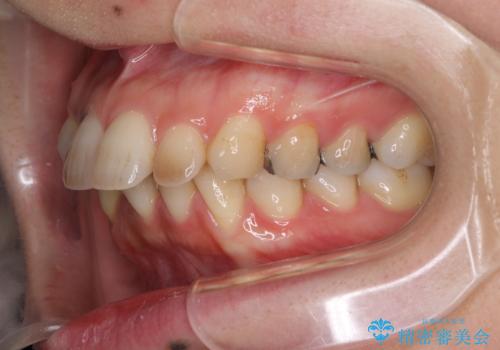

- 上下の出っ歯を気にして来院された患者様です。

口元を積極的に引っ込めるために、上下左右の第一小臼歯を4本抜歯することとしました。

元々ディープバイトのため、スペースを閉じている期間に上下前歯が接触してしまい、治療期間が想定よりも伸びてしまいました。